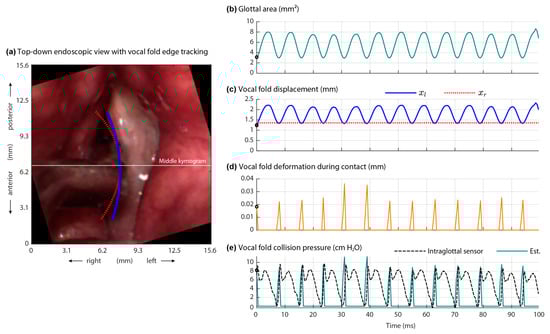

Figure 5 shows the results of the contact pressure analysis method that incorporated a Hertzian model of collision []. Plotted are the input measured variables to the model from the high-speed videoendoscopy imaging data (calibrated glottal area and vocal fold displacement) and output estimated parameters from the model (vocal fold deformation at contact and vocal fold collision pressure). See Video S4 (Supplementary Materials) showing a movie of Figure 5 that plots over time the input and output variables overlaid on the high-speed videoendoscopy frames. Direct comparison between the estimates of collision pressure from the model and the measured intraglottal pressure sensor signal is illustrated in Figure 5 as well. The impact stress component matches the first peak of the measured intraglottal signal well. The root mean square error between the estimated collision pressure peaks and the measured peak collision pressures across all cycles in this 100 ms phonatory segment was 1.04 cm H2O, corresponding to a mean absolute error of 0.81 cm H2O and mean absolute percentage error of 9.1%. The resulting contact pressure component is in good agreement with prior numerical studies [].

Figure 5. Results of the Hertzian contact pressure analysis method of Díaz-Cádiz et al. []. Shown are the (a) first high-speed videoendoscopic frame with vocal fold edge tracking, (b) measured glottal area waveform, (c) vocal fold displacement at the middle digital kymogram of the left (xl) and right (xl) folds using a Kalman filter, (d) vocal fold deformation during contact (model output), and (e) vocal fold collision pressure as estimated by the model (Est.) and directly measured by the ISP probe’s intraglottal sensor.